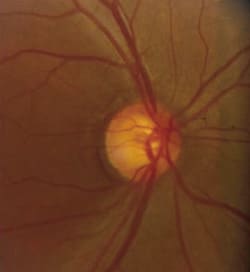

Fig. 3. Advanced loss of the neuroretinal rim and diffuse thinning of the nerve fiber layer in a patient with advanced

glaucoma. |

Early changes associated with glaucomatous optic neuropathy include: Generalized enlargement of the cup, focal enlargement of the cup (Figure 3), increased cup/disc ratio, acquired pit of the optic nerve, notching or narrowing of the neuroretinal rim, isolated disc hemorrhage, peripapillary atrophy (Figure 4), focal loss of the nerve fiber layer (Figure 5), translucency of the neuroretinal rim, baring of circumlinear vessel (Figure 6) and asymmetric cupping between the patient's two eyes.14